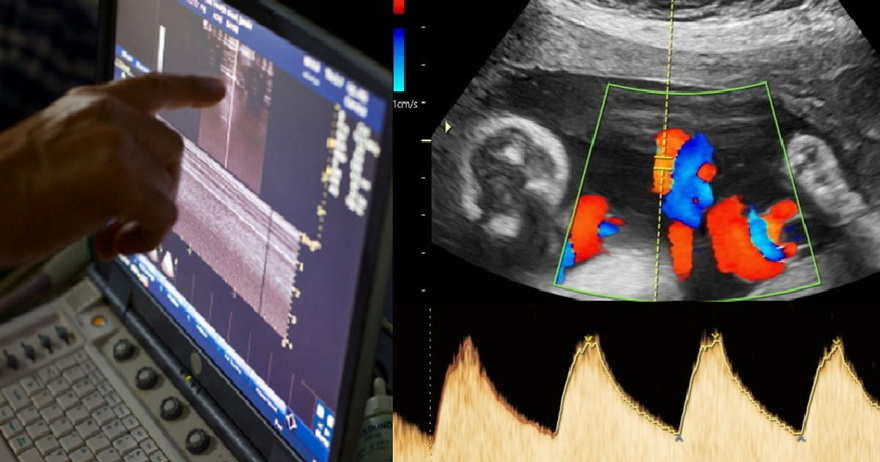

Το ζευγάρι είχε κάνει πολλές προσπάθειες εξωσωματικής γονιμοποίησης και είχε επισκεφθεί κέντρα υποβοηθούμενης αναπαραγωγής σε διάφορες χώρες, με την ελπίδα να αποκτήσει παιδί. Η εξωσωματική γονιμοποίηση περιλαμβάνει την αφαίρεση ωαρίων από τη γυναίκα και τη γονιμοποίησή τους στο εργαστήριο με σπέρμα, ώστε να δημιουργηθεί έμβρυο, το οποίο εμφυτεύεται στη μήτρα.

Ωστόσο, για το συγκεκριμένο ζευγάρι οι προσπάθειες δεν είχαν αποτέλεσμα, λόγω αζωοσπερμίας — μιας σπάνιας κατάστασης κατά την οποία δεν ανιχνεύεται καθόλου σπέρμα στο δείγμα του άνδρα. Ένα φυσιολογικό δείγμα σπέρματος περιέχει εκατοντάδες εκατομμύρια σπερματοζωάρια, αλλά στους άνδρες με αζωοσπερμία ο αριθμός είναι τόσο χαμηλός που δεν εντοπίζεται κανένα σπερματοζωάριο, ακόμα και μετά από ώρες αναζήτησης στο μικροσκόπιο.

Η μέθοδος αυτή λέγεται STAR και χρησιμοποιεί τεχνητή νοημοσύνη για να εντοπίσει και να ανακτήσει κρυμμένα σπερματοζωάρια σε άνδρες που θεωρείται ότι δεν έχουν καθόλου σπέρμα. Το μόνο που χρειάστηκε ο σύζυγος ήταν να δώσει ένα δείγμα σπέρματος στην ιατρική ομάδα.

Οι ειδικοί ανέλυσαν το δείγμα με το σύστημα τεχνητής νοημοσύνης και βρήκαν τρία κρυμμένα σπερματοζωάρια, τα οποία ανακτήθηκαν και χρησιμοποιήθηκαν για να γονιμοποιήσουν τα ωάρια της συζύγου μέσω εξωσωματικής.

Η γυναίκα έμεινε έγκυος — είναι η πρώτη επιτυχία με τη μέθοδο STAR — και το μωρό αναμένεται να γεννηθεί τον Δεκέμβριο.